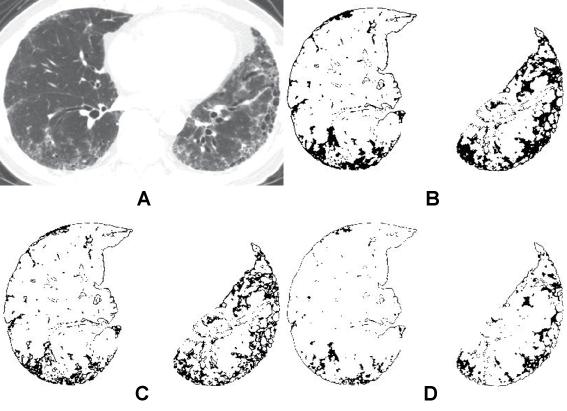

For the evaluation of the extent of interstitial fibrotic change, the lung field was segmented using a threshold technique with all pixels between -200 and -1024 HU [12,13]. When auto segmentation was difficult due to the presence of the sub pleural fibrosis, the boundary of the lung field was traced manually. In reference to previous studies, total interstitial lesion was defined as high attenuation area (HAA) using a threshold with all pixels between 0 and -700 HU [2,11-13]. Also areas with different lung attenuation ranges of -500 and -700 HU, and 0 and -500 HU were calculated. The mean percentage of each HAA in different attenuation ranges was obtained by calculating the mean percentage of each HAA (%HAA0/-700, %HAA-500/-700, and %HAA0/-500, respectively) (Figure 1).

Figure 1 a) Axial CT section of the lung shows segmented area using;

b) Pixels with attenuation range between 0 and -700 HU are highlighted in black on the CT scan. The mean percentage of high attenuation area (%HAA0/-700) is calculated as the percentage of the lung attenuation area between 0 and -700 HU for the total lung area;

c) Pixels with attenuation values between -500 and -700 HU are highlighted in black on the CT scan. The mean percentage of high attenuation area (%HAA-500/-700) is calculated as the percentage of the lung attenuation area between -500 and -700 HU for the total lung area;

d) Pixels with attenuation values between 0 and -500 HU are highlighted in black on the CT scan. The mean percentage of high attenuation area (%HAA0/-500) is calculated as the percentage of the lung attenuation area between 0 and -500 HU for the total lung area.